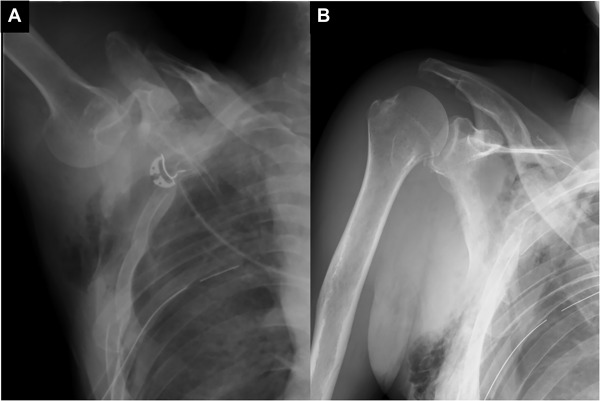

Recurrent Dislocation

Recurrent dislocation implies having repeated dislocations of the shoulder. Patients with a tendency for recurrent (repeated) dislocation or subluxation are said to have an unstable shoulder or shoulder instability (unstable shoulder). Shoulder instability may follow after a traumatic dislocation (after a fall or injury to the shoulder), due a generalized laxity of ligaments, or due to gradual stretching of the joint capsule due to a repetitive injury as in a throwing athlete.